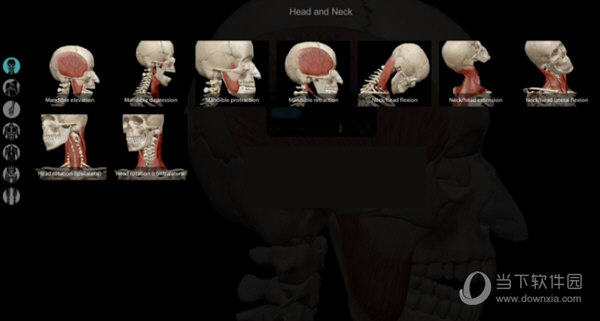

8、点击Media,可以查看人体部位的动画,展示人体活动时的状态。